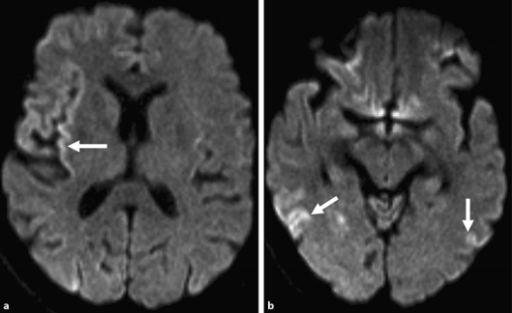

Definition & diagnosis, clinical presentation and treatment. The national institute of neurological disorders and. The characteristic eeg shows biphasic or triphasic discharges that are initially sporadic and may even be asymmetric.

People with cjd and vcjd show a characteristically abnormal pattern. Read and know all about this disease, including its causes, symptoms, diagnosis and treatment options. Over the course of weeks to months, it causes the brain tissue to degenerate rapidly, and the cortex develops holes and the texture changes to resemble that of a kitchen sponge. It is a rare but serious disorder.